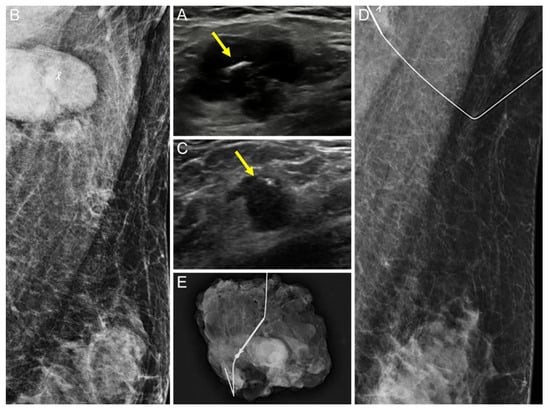

Comparison of the Ultrasound Visibility of Tissue Markers in Metastatic Lymph Nodes after Neoadjuvant Chemotherapy in Patients with Breast Cancer

3.1. Comparison of the US Visibility between the Two Tissue Markers after NAC